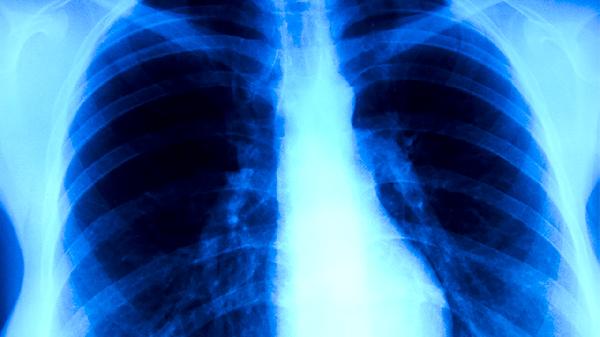

少数情况下支原体肺炎可能发展为严重症状,持续高热超过3天提示病情较重。剧烈咳嗽影响睡眠和日常活动时需要警惕。胸痛可能提示肺部炎症累及胸膜,呼吸困难是病情加重的信号,可能出现呼吸急促、口唇发绀等表现。婴幼儿、老年人以及存在基础疾病的患者更容易出现严重症状,可能并发胸腔积液、肺不张等。对于出现严重症状的患者,应及时就医进行胸部影像学检查,必要时住院治疗。